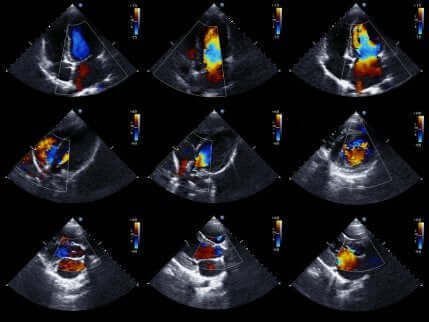

Ekkokardiogrammer, eller hjertesonogrammer, lar til slutt medisinsk fagfolk studere hjertet mer detaljert.

Ekkokardiogrammet er en veldig populær medisinsk test. Dette er fordi den får bevegelige bilder av hjertet. Dermed kan den evaluere statusen til hjertekamrene og deres bevegelser for å bekrefte eller utelukke iskemi.

I tillegg evaluerer den også hjertestørrelse og -styrke, samt tilstanden til veggene i hjertets kamre. Totalt sett er det en ikke-invasiv test som ikke innebærer noen risiko for pasienten. Dette er fordi den bruker ultralyd for å få tak i bilder av hjertet.

Hvis legen bruker denne testen, utelukker fraværet av bevegelsesforstyrrelser i hjerteveggen tilstedeværelsen av iskemi. Tross alt er ikke bevegelsesforstyrrelser unike for akutt koronarsyndrom. Av den grunn skal testresultatene og symptomene vurderes sammen.